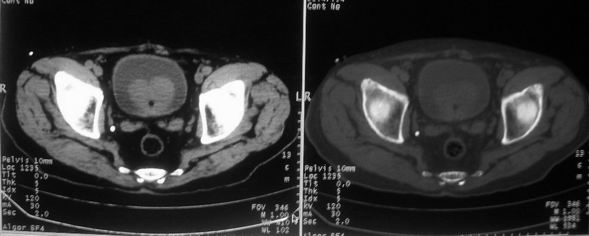

男,85岁,排尿困难。骶椎有问题吗?

前列腺明显增大,突入膀胱,各叶比例协调,密度均匀,精囊腺及精囊角正常;考虑良性增大。

骶骨没有看到明显异常。

这个病人排尿困难应该是前列腺增生造成的,ct对前列腺增生及前列腺癌诊断有一定限度,只能判断前列腺增大,建议还是做一个mr来鉴别一下增生或癌更好,因为增生多发生于中央带,癌多发生于周围带,而mr t2加权图像上中央带和周围带的信号有区别,因此诊断价值更高一些。

1)前列腺明显增大,突入膀胱,各叶比例协调,密度均匀,精囊腺及精囊角正常;考虑前列腺增生症并阻塞性膀胱炎。2)骶椎右侧类似囊状骨质密度减低区,边缘骨质硬化,其内为软组织密度影填塞,相邻之骶椎椎管受压变形;考虑为骶椎右侧囊肿或神经纤维瘤。

建议:行mri检查。